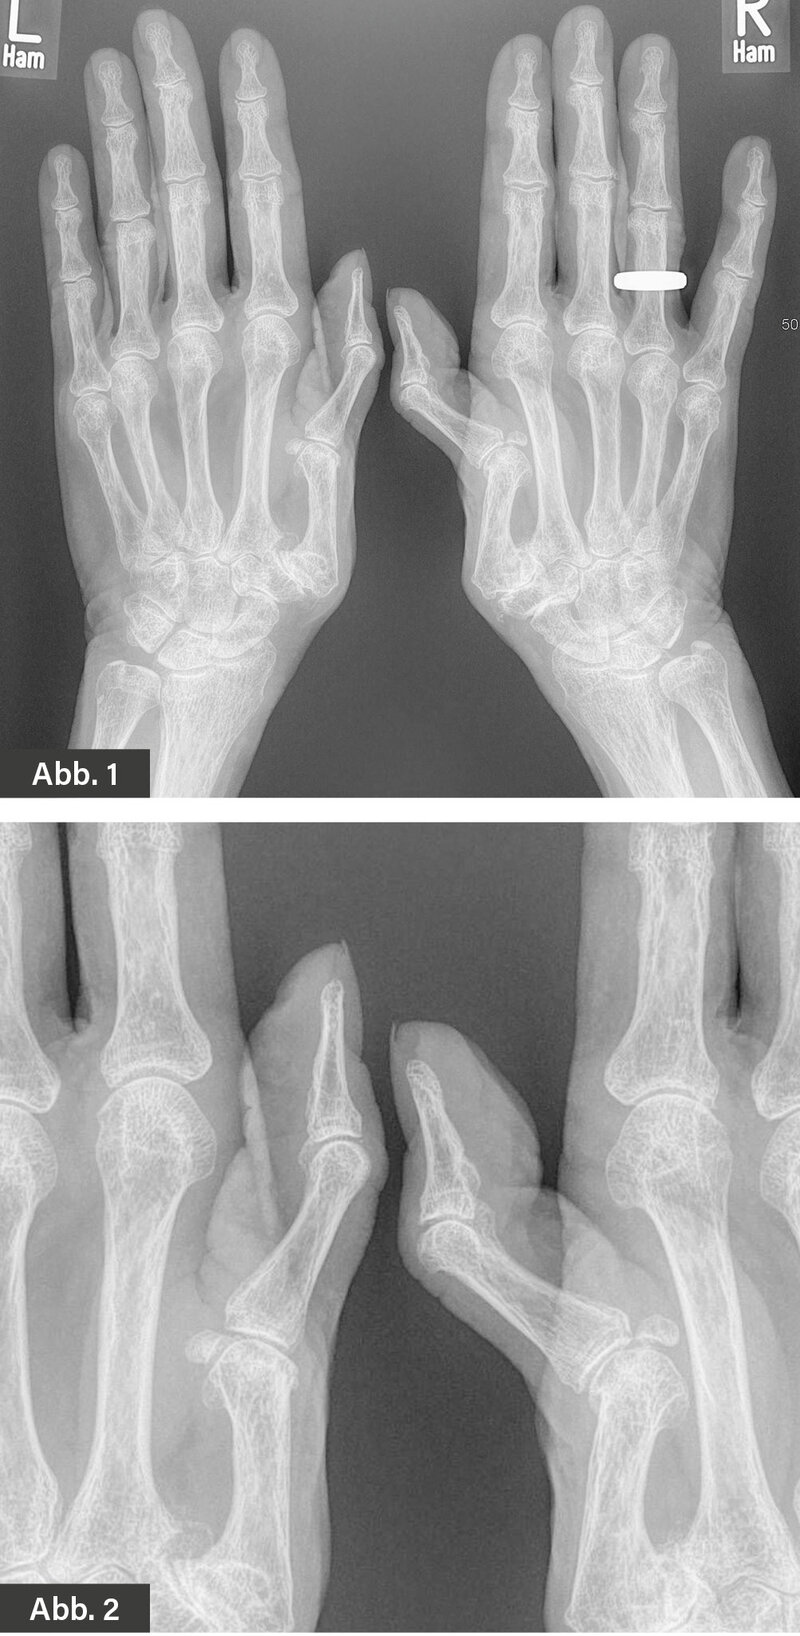

BILDGEBENDE DIAGNOSTIK: Röntgen (Abbildung 1 und 2)

DIAGNOSE: 90-90-Deformität (Z-Daumendeformität)

Bei der 90-90-Deformität handelt es sich um eine Fehlstellung/Deformierung des Daumens, die im Rahmen einer rheumatoiden Arthritis oder aber auch im Rahmen degenerativer Gelenkerkrankungen (Fingerpolyarthrose) auftreten kann. Sie ist meist beidseitig.

Die 90-90-Deformität kann als eine Unterart der Schwanenhalsdeformität angesehen werden. Die Schwanenhalsdeformität betrifft dreigliedrige Finger, die 90-90-Deformität dagegen den zweigliedrigen Daumen. Das Daumengrundgelenk ist dabei um etwa 90° gebeugt, das Daumenendgelenk jedoch überstreckt, sodass sich die charakteristische Form ergibt. Ursächlich hierfür sind Gelenkveränderungen und insbesondere Schäden am Kapsel-Bandapparat im Bereich des Daumengrund- und -sattelgelenks.